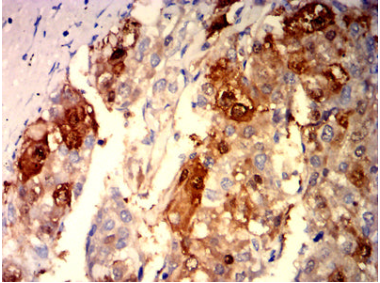

ARG1 Mouse Monoclonal antibody[6B4B1]

AC1156 ARG1 Mouse Monoclonal antibody[6B4B1] 100ug $367 10days

IHC    1/200-1/1000